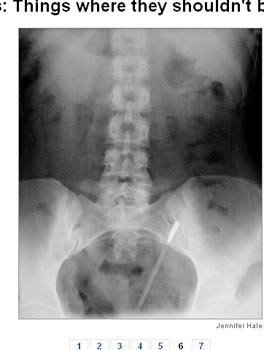

Hai trường hợp trên, các bác sĩ đã để quên kéo trong bụng của bệnh nhân sau khi phẫu thuật. Trường hợp thứ hai, trong cơ thể bệnh nhân có tới 2 cái kéo.